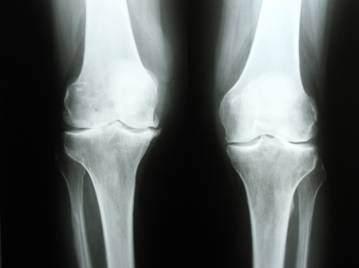

Рентген коленного сустава

Самый простой, быстрый и доступный метод диагностики патологических состояний коленного сустава. Коленные суставы испытывают немалую нагрузку, особенно, когда человек ведет активный образ жизни и занимается спортом, поэтому болезни и травмы в области колена встречаются довольно часто. Показаниями к проведению рентгена коленного сустава могут быть любые повреждения и травмы, болезненность колена в покое и при движении, припухлость сустава, изменение цвета кожи над коленом, ограничение подвижности, деформация колена.

Рентген колена имеет большую диагностическую ценность, прежде всего при травматических повреждениях, среди которых: трещины костей; переломы, подвывихи и вывихи сустава; травмы связочного аппарата; кровоизлияния в коленный сустав; переломы мыщелков, травмы менисков и надколенника и др.